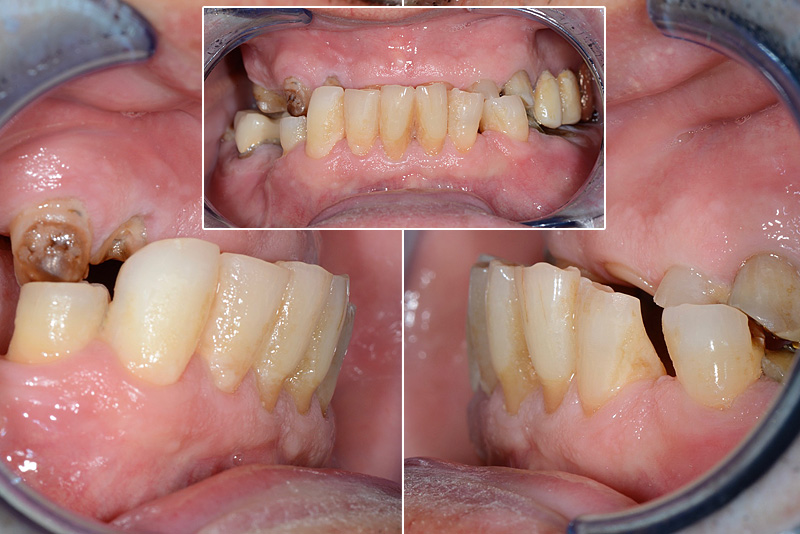

PREMESSA: in seguito all’estrazione dell’incisivo laterale superiore di destra, resasi necessaria per cause batteriche, si decide di affrontare il caso con il posizionamento di un impianto in sostituzione dell’elemento mancante dopo guarigione del sito infetto. Con tecniche rigenerative sia dei tessuti ossei mancanti a causa dell’infezione pregressa, sia dei tessuti gengivali che appaiono inizialmente troppo spostati in alto, si ripristina una corretta morfologia delle parabole (contorni) gengivali e delle papille interdentali (triangoli di gengiva tra due denti vicini).

Vengono utilizzati 2 tipi di provvisori: il primo, cementato ai denti vicini, viene utilizzato dal momento dell’estrazione del dente fino ad impianto osteointegrato (circa 6 mesi); il secondo, avvitato direttamente all’impianto, ha una funzione di prova estetica ma soprattutto di guida per la maturazione dei tessuti gengivali peri-implantari portandoli verso la maturazione completa prima di posizionare la corona finale in disilicato di litio.